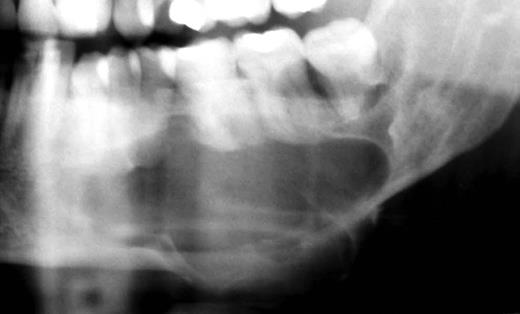

The panoramic radiography shows a large radiolucent and well-defined lesion with a radiopaque corticates margin involving the left mandibular premolar and molar (Fig. 2).

The panoramic radiography shows a large radiolucent and well-defined lesion with a radiopaque corticates margin involving the left mandibular premolar and molar area.